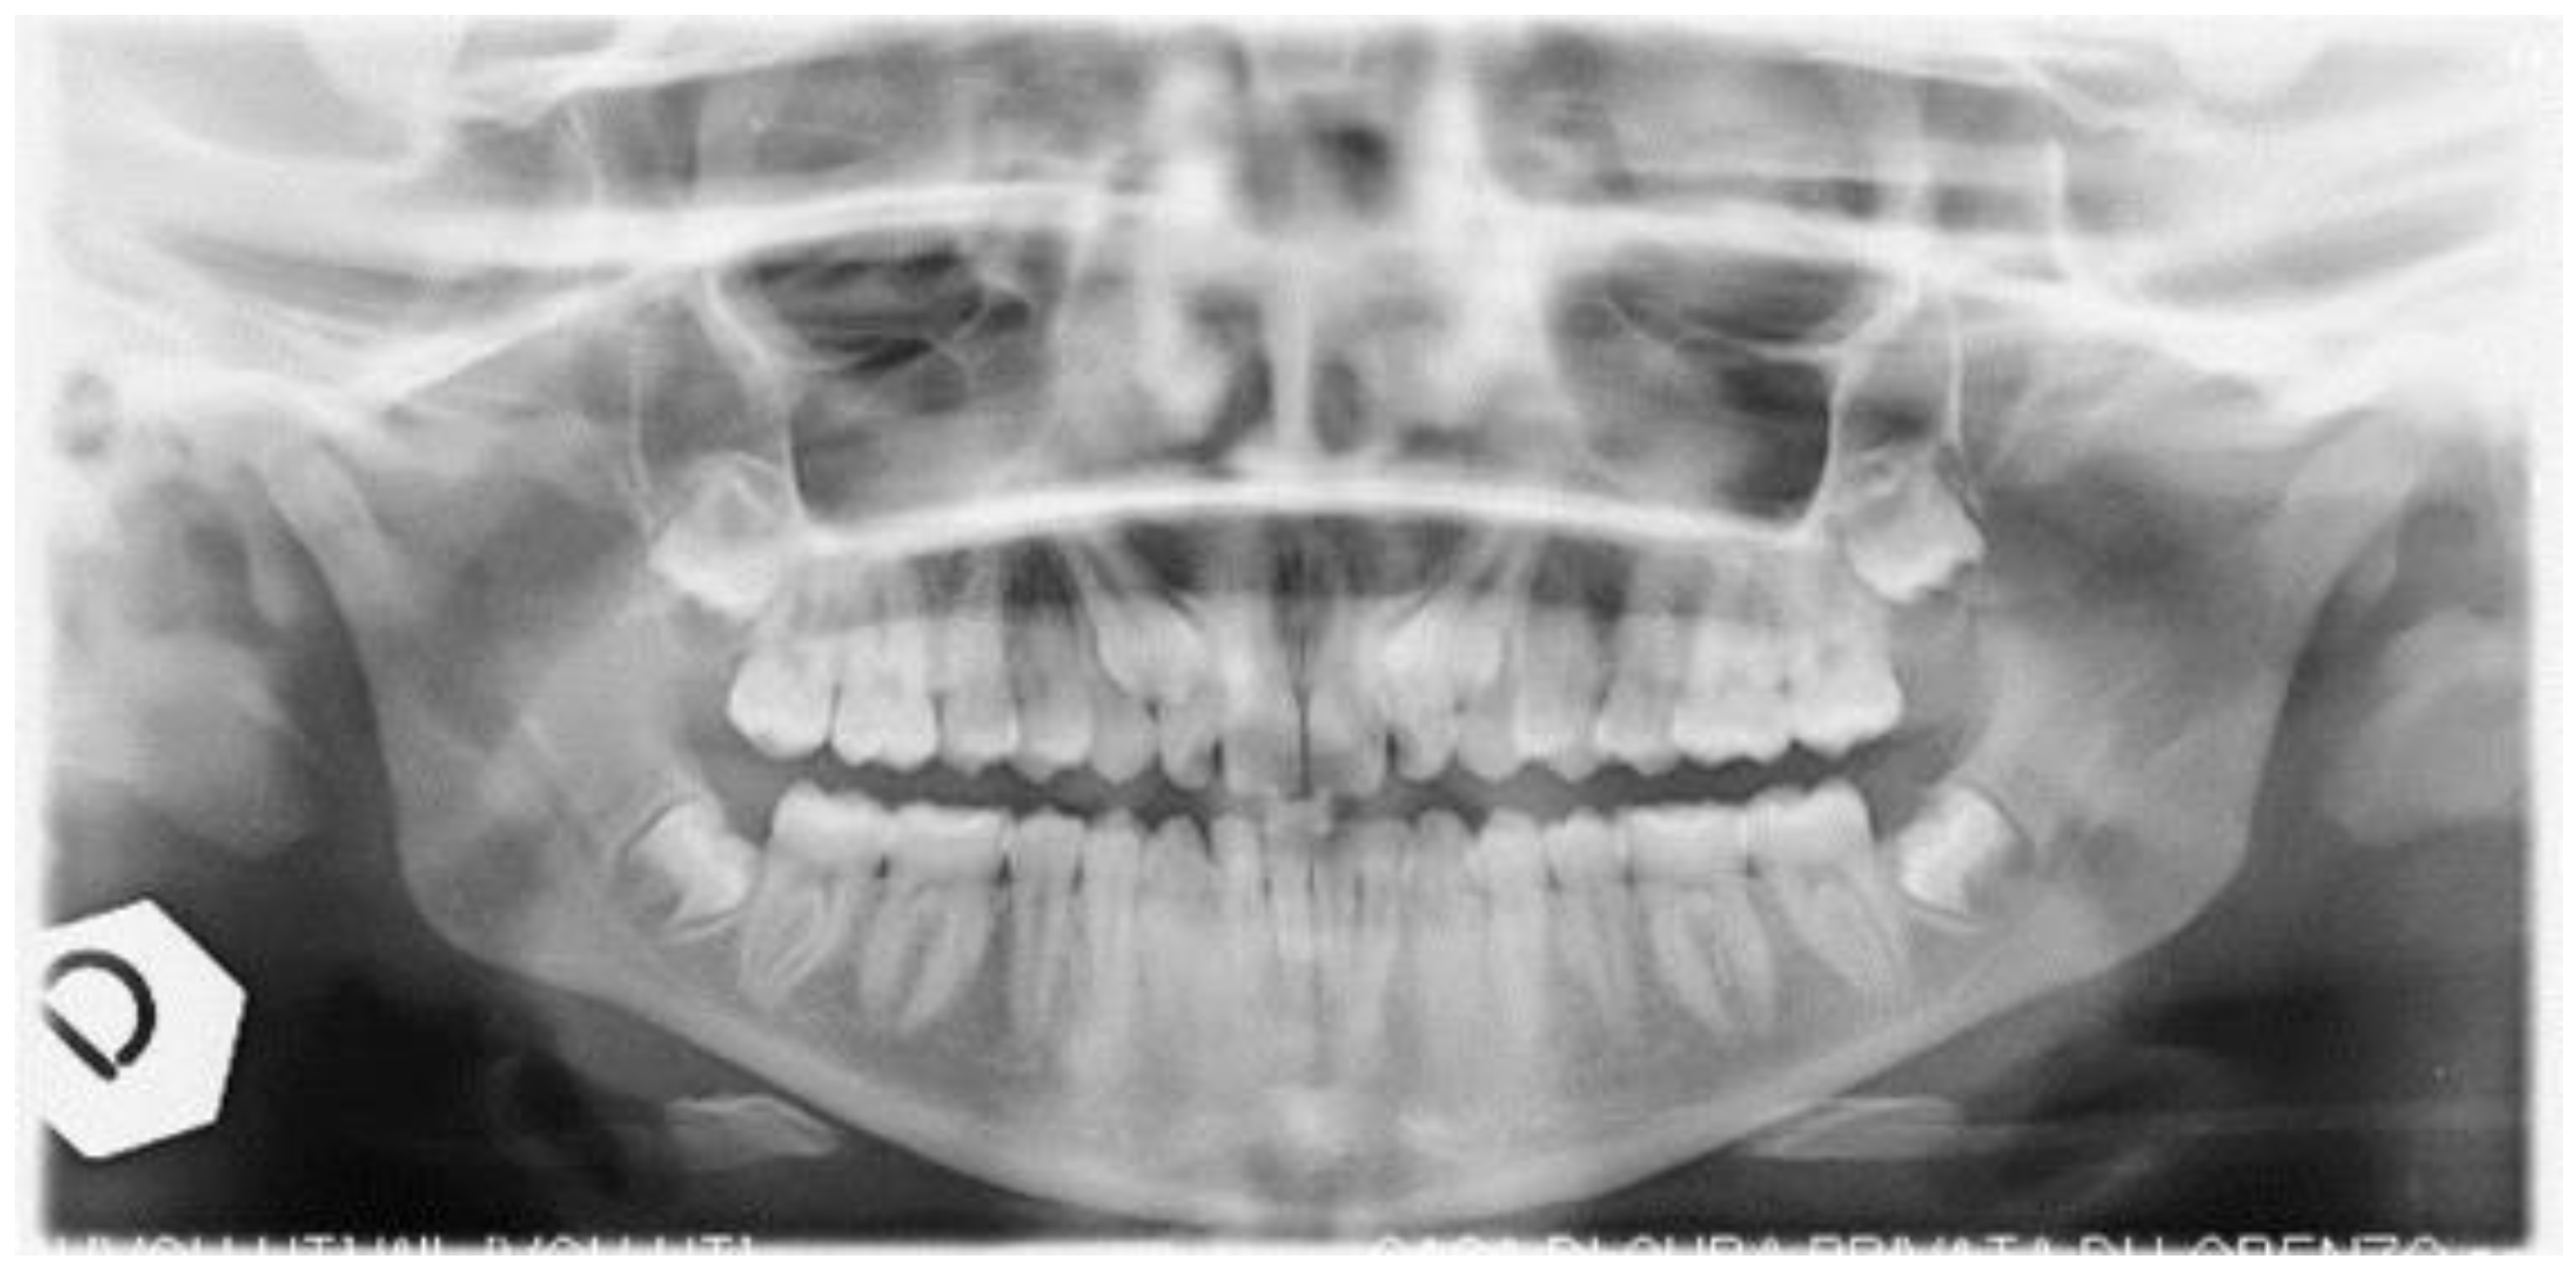

2. Case Presentation